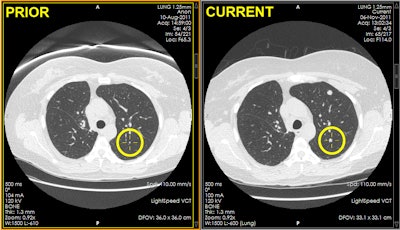

At follow-up, radiologists must match nodules between prior exams and the current study. This process is performed by locating the nodule on the prior study, typically by using the prior radiology report as a guide. The radiologist then finds the nodule on the current study or the region where the nodule was located if it has been resolved, he said.

In the absence of registration, nodule localization can take considerable time, effort, and cost, and it can be challenging to locate the same nodule in current and prior studies. Patient positioning can vary, as can the overall degree of breath-holding and the lung, lobe, or segment expansion between the current and prior exams. There may have also been surgical or radiation intervention during the interval, Barish said.

Image registration between current and prior exams reduces the time needed to locate nodules, and rigid registration (i.e., synchronized scrolling) techniques are available on nearly all PACS software, he said. Deformable registration, however, is not currently available on most PACS workstations.

There were 112 total nodules identified on prior studies, and the researchers determined the series and slice number as well as anatomical location for each nodule on the first study, which was considered the "prior" exam. Two board-certified radiologists were then given the nodule location on the prior study and were asked to match each nodule on the prior study to a location on the current exam.